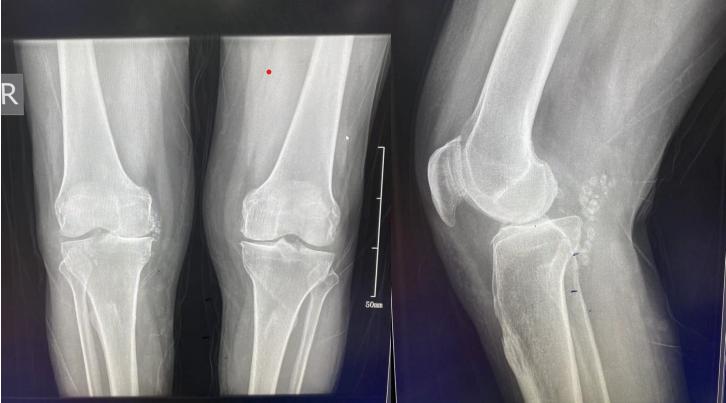

这是马大爷术前X片

这是马大爷术后X片